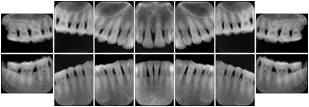

In most standard cases, images are oriented in structured layouts. These structured displays are useful to be shared between providers for reference purposes.

Table OO.1.1-1 shows structured display standard templates, where Viewset ID is based on the Japanese Society for Oral and Maxillofacial Radiology (JSOMR) classification provided by JIRA (Japan Medical Imaging and Radiological Systems Industries Association, www.jira-net.or.jp). Expected or typical teeth to be imaged location, region and designation codes are based on ISO 3950-2010, Dentistry - Designation system for teeth and areas of the oral cavity. For all the hanging protocols listed in OO.1.1-1, the value to use for Hanging Protocol Creator (0072,0008) is "JSOMR" and the value to use for Hanging Protocol Name (0072,0002) does not include "JSOMR" (e.g., "DL-S001A", not "JSOMR DL-S001A").